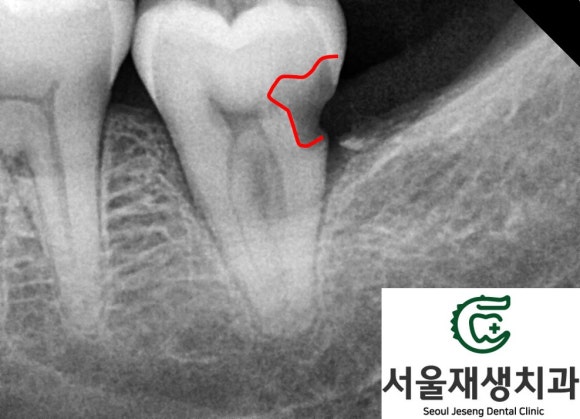

위 환자분은 다행히

충치가 치아 머리와 뿌리 사이에

아슬아슬하게 걸쳐있어서

현미경을 통해 충치를 세심하게

제거할 수 있다면

충분히 치료를 시도해볼만하다고

판단했습니다.

신경까지 진행된 충치를 제거하고

신경치료를 시행합니다.

현미경을 이용하여

충치를 섬세하게 제거하고

신경치료를 진행하였습니다.